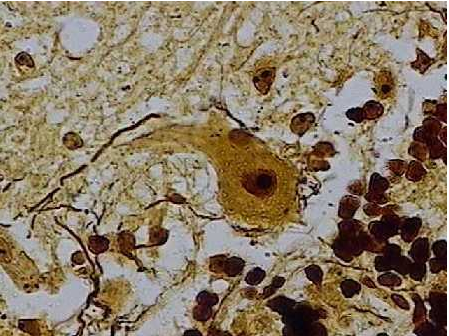

Fotomicrografia de um neurônio motor;

Os neurônios são formados por um corpo celular ou pericárdio, que contém núcleo e do qual partem prolongamentos. Em geral, o volume total dos prolongamentos de um neurônios é maior do que o volume do corpo celular.

Os neurônios possuem morfologia complexa, porém quase todos apresentam três componentes:

Dendritos: Prolongamentos numerosos, especializados na função de receber os estímulos do meio ambiente, de células epiteliais sensoriais ou de outros neurônios;

Corpo Celular: É centro trófico da célula e é também capaz de receber estímulos;

Axônio: Um prolongamento único,especializado na condução de impulsos que transmitem informações do neurônio para outra células.